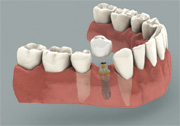

Missing a tooth ? An Implant can replace that missing tooth in no time. Modern dental implants are precision devices, the most common type is a titanium screw that is anchored into the jawbone where it serves as post for a custom-made tooth crown. Once the crown is in place, you may not be able to tell it apart from your natural teeth.

Implant with a crown